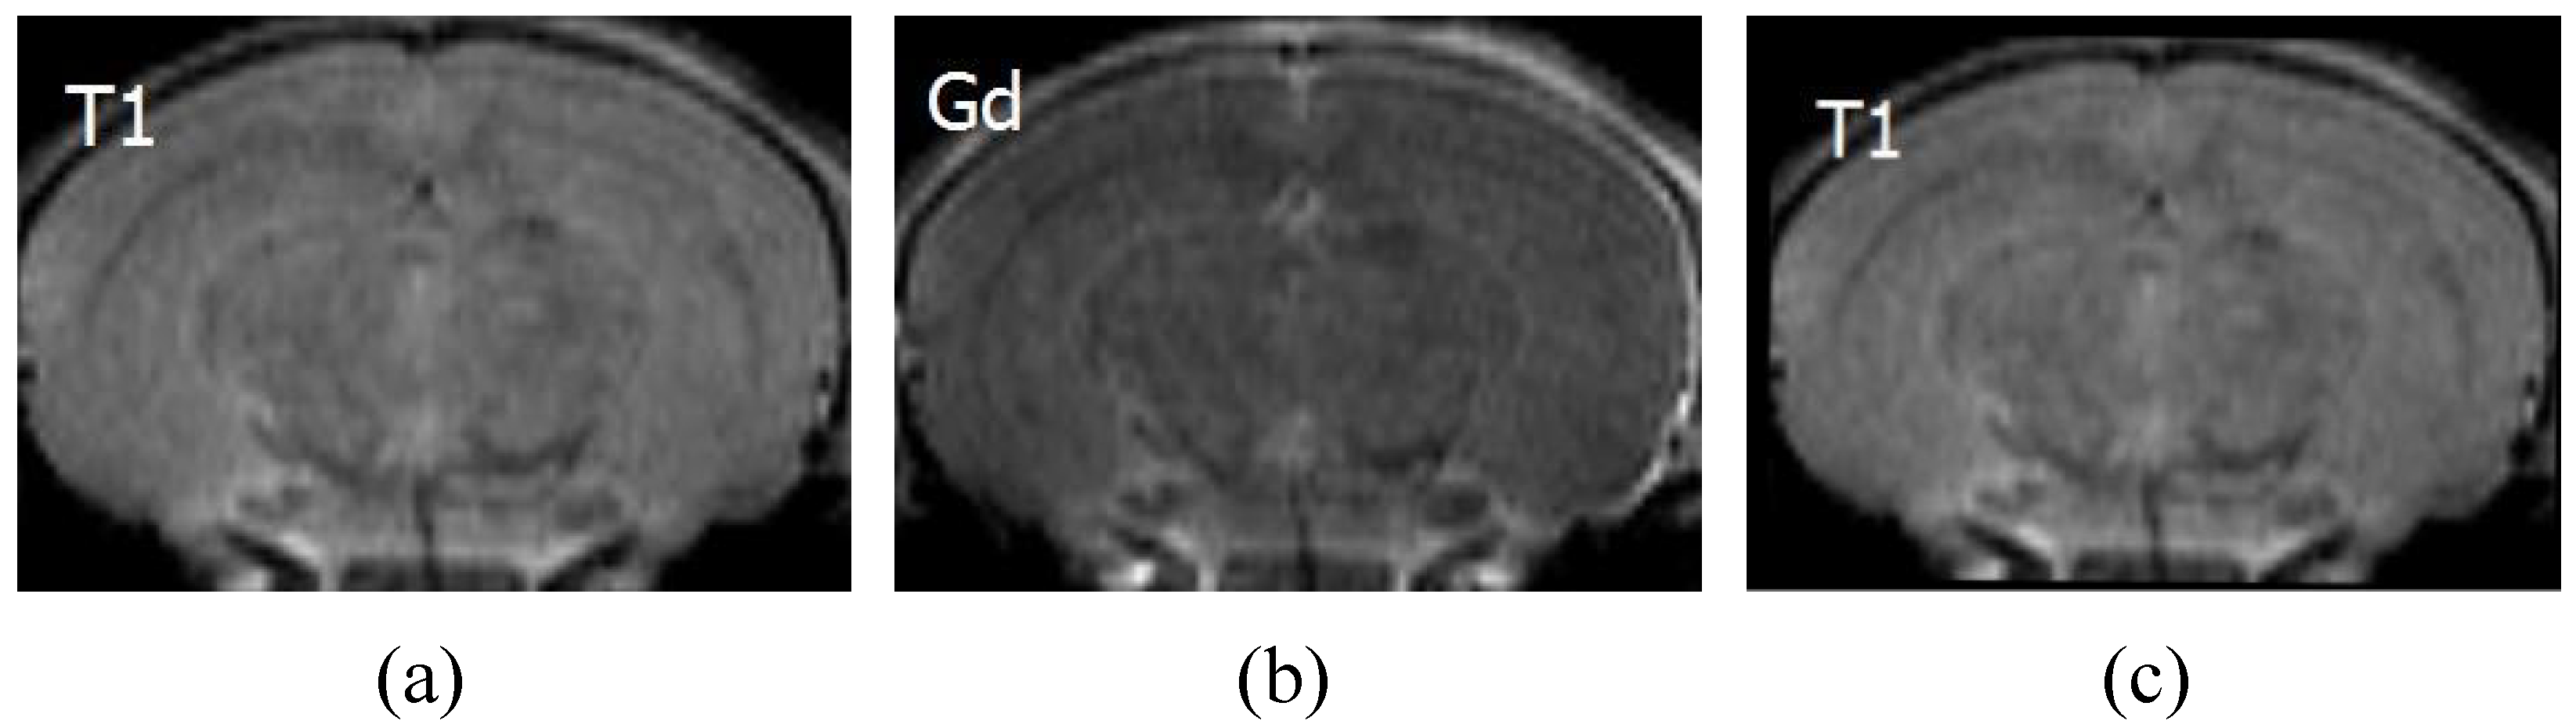

The feasibility of applying IFSrNet to other multimodal image registration tasks has been tried in medical images [47]. Chemical exchange saturation transfer (CEST) is a magnetic resonance imaging (MRI) technique for enhancing the contrast of images, which indirectly identifies the metabolites in tissue at millimolar concentrations through the water proton signal. Because the samples must have a sufficient saturation frequency, a large time span is usually required to acquire the spectrum. It is important to note that subject movement throughout the scan can lead to errors in CEST quantification. Even minor movements can have a significant impact on CEST analysis, resulting in the appearance of unusual peaks or dips in the spectrum and an uneven signal distribution on the image. To mitigate motion artefacts, image registration is a commonly employed method to ensure high-quality CEST-MRI images. Figure 15 shows the application of IFSrNet for registering T1 and Gd image pairs in CEST-MRI images of a rat brain. The lack of an objective gold standard for assessing the registration results of medical images means that the physician’s judgement is crucial. After observation by senior experts, IFSrNet was able to accurately reconstruct the target images, which illustrates the potential of the network’s application. All the CEST-MRI images in this experiment were obtained from Johns Hopkins University.

Figure 15. CEST-MRI images for a rat stroke lesion in which (a) is T1 as the image registration to be registered, (b) is Gd as the reference, and (c) is the T1 image that has been registered.